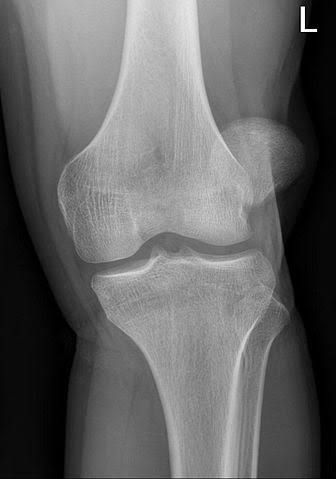

Patellar malalignment is a translational or rotational deviation of the patella relative to any axis that may lead to an aberrant dispersion of the forces transmitted through the PF joint (17). The main force of concern is lateral in the coronal and especially axial planes (18).